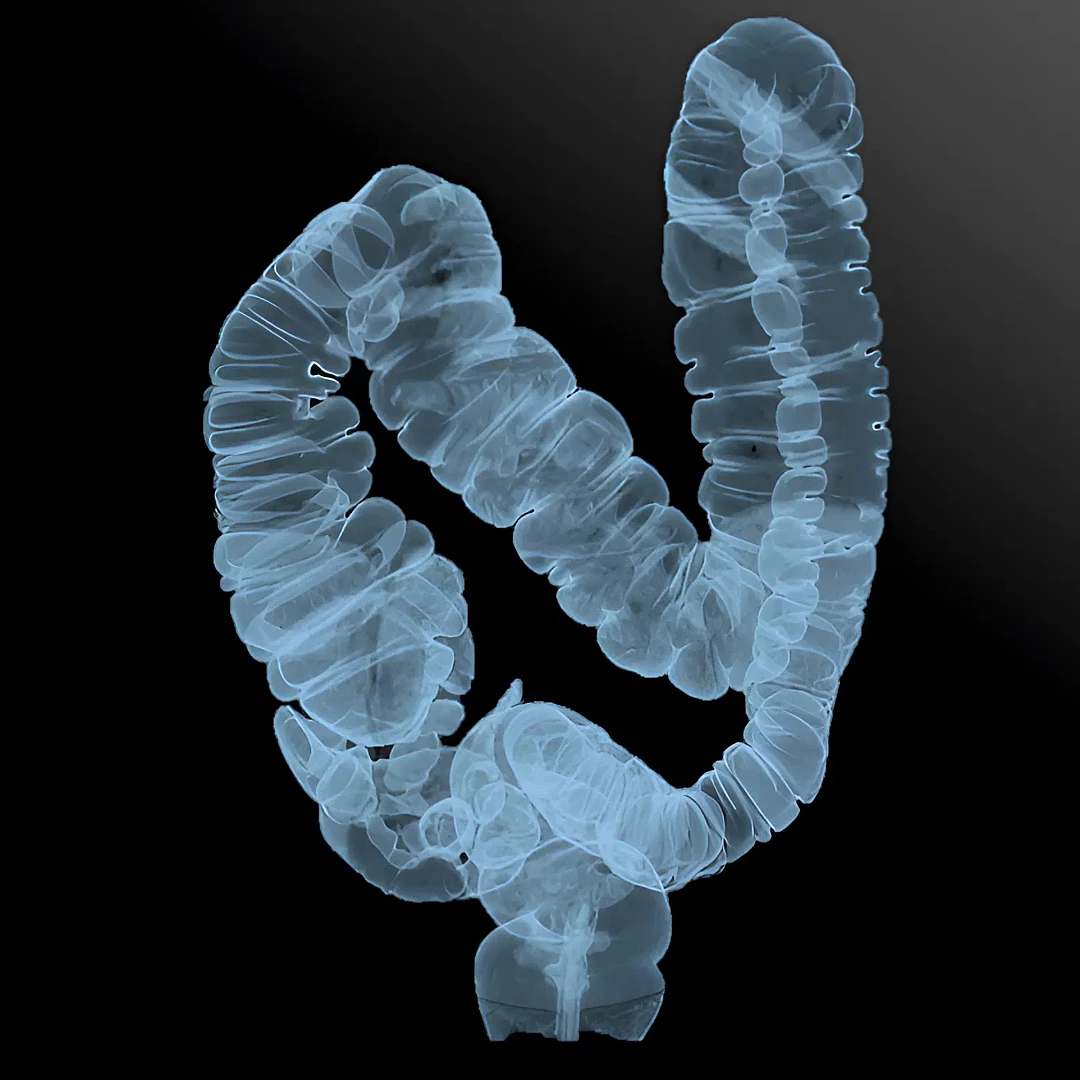

Virtual Colonoscopy CT uses advanced imaging to create a 3D view of the colon, detecting polyps or tumors without traditional colonoscopy. It’s a quick, non-invasive screening option for colorectal cancer.